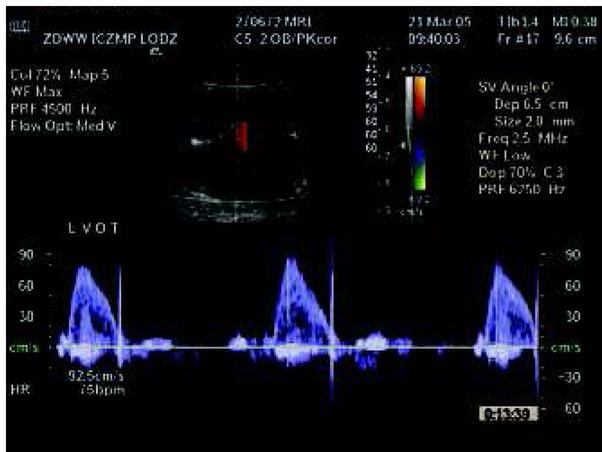

Fig. 6

Isolated complete heart block in Doppler evaluation in a fetus with normal heart anatomy.Ryc. 6. Izolowany blok serca płodu (przy prawidłowej budowie serca) w badaniu za pomocą Dopplera.